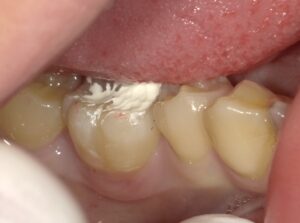

MTAセメントは必ずラバーダムというゴムを装着し

唾液が浸潤しないようにします。

MTAセメントを詰めたところです。

仮のセメントで少し経過を見ます。